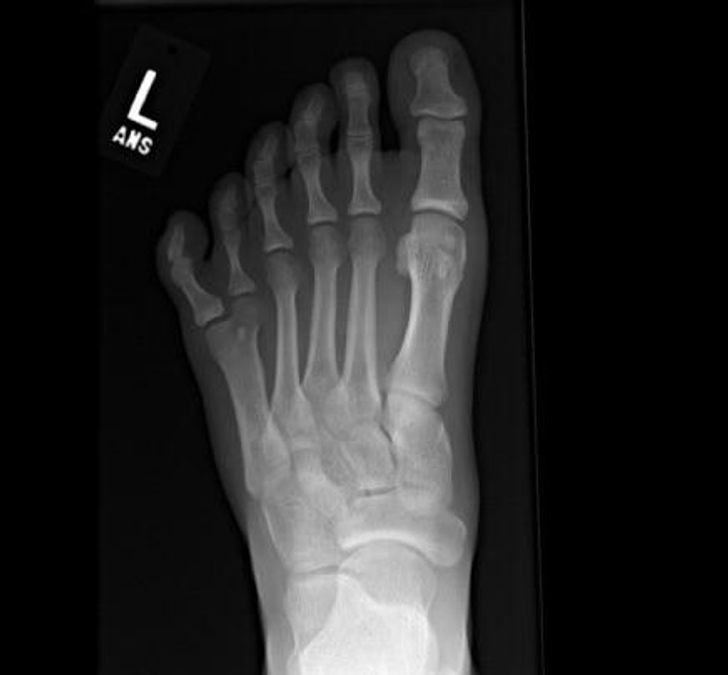

12. Hexadactyly, the word for having an extra toe

Illustration de l'article : 14 X-ray images that reveal a hidden story

© DomnLee / Reddit